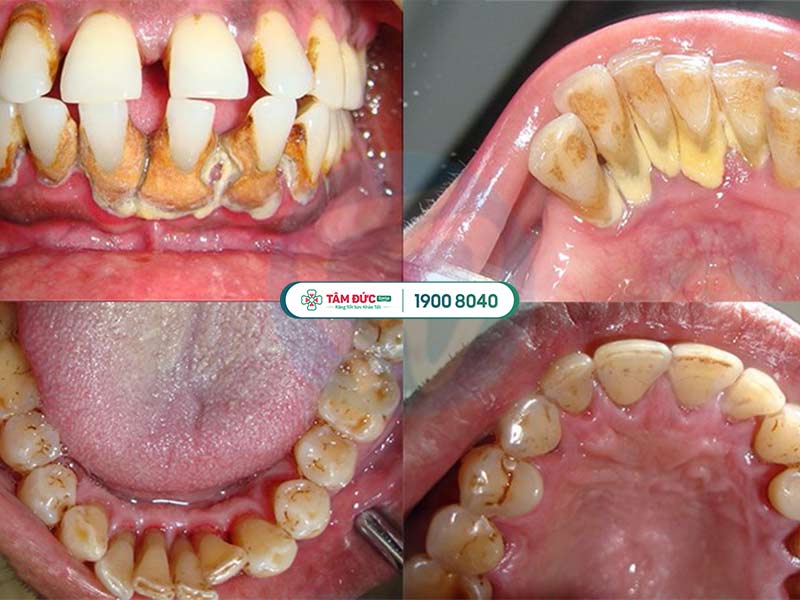

Vôi răng được hình thành từ thức ăn dư hàng ngày, không thể loại bỏ triệt để, bám chặt vào thân răng. Vôi răng là nơi tồn tại rất nhiều vi khuẩn gây viêm nhiễm, vôi răng lâu ngày không được loại bỏ chính là “căn cứ” tốt nhất để vi khuẩn tấn công vào răng và nướu. Thông thường những đốm sâu nhỏ sẽ xuất hiện xung quanh chỗ nhiều vôi răng, đôi khi vùng sâu bị vôi răng che mất nên chỉ khi răng đau nhức do sâu vào đến tủy thì bệnh nhân mới phát hiện ra. Ngoài sâu răng, vôi răng không được vệ sinh định kỳ sẽ khiến cho bệnh nhân bị viêm, nhiễm phần nướu, dẫn đến các bệnh viêm nướu, viêm nha chu,... thậm chí gây mất răng từ từ.

Cao răng là nguyên nhân chủ yếu dẫn đến sâu răng và hôi miệng